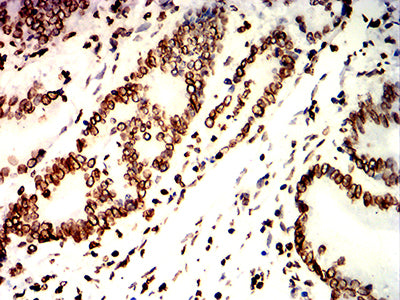

Immunohistochemical analysis of paraffin-embedded human colon cancer tissues using LMNB1 mouse mAb with DAB staining.